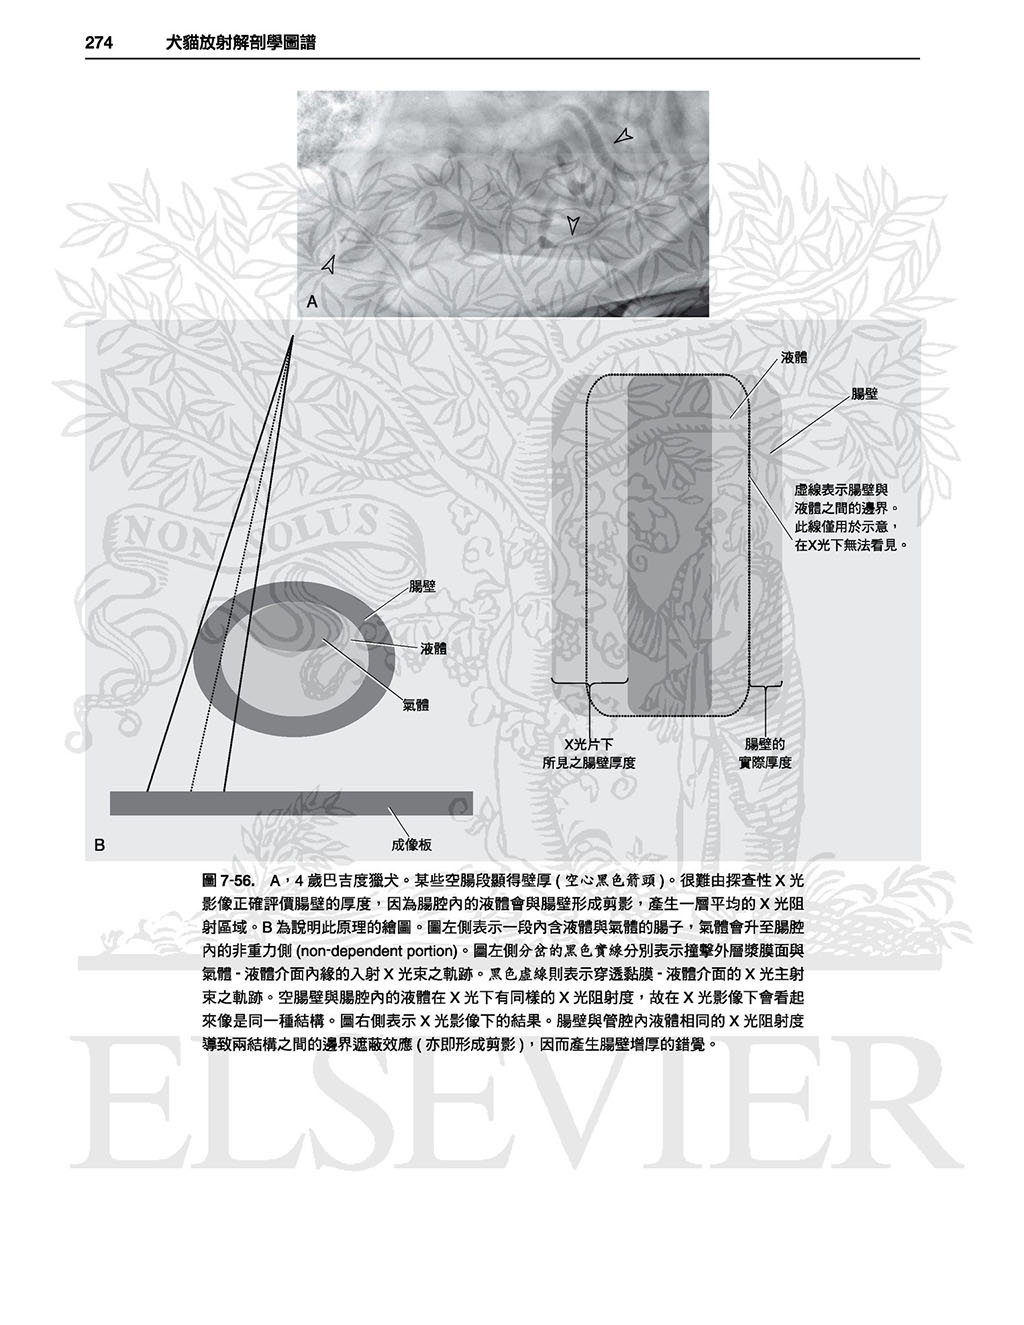

7腹腔, 231